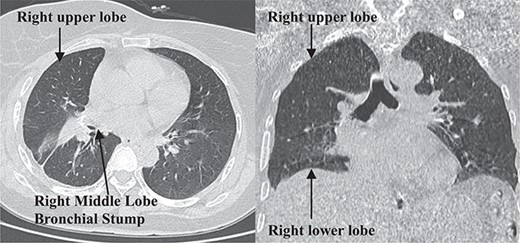

The patient was admitted on 20 March 2024. Enhanced chest CT revealed a solitary cystic lung lesion in the right middle lobe, measuring 8.0 cm × 7.3 cm, with a thin wall and slight compression of the right cardiac border (Fig. 1).

A follow-up chest CT scan 1-month post-surgery showed no pneumothorax, pleural effusion, or pneumonia (Fig. 4). The patient reported no symptoms of cough, sputum production, chest tightness, or shortness of breath and exhibited good daily activity performance.

Postoperative 1-month follow-up non-contrast chest computed tomography.